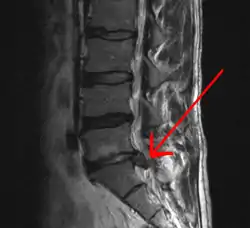

In most episodes of low back pain, a specific underlying cause is not identified or even looked for, with the pain believed to be due to mechanical problems such as muscle or joint strain.[1][4] If the pain does not go away with conservative treatment or if it is accompanied by "red flags" such as unexplained weight loss, fever, or significant problems with feeling or movement, further testing may be needed to look for a serious underlying problem.[5] In most cases, imaging tools such as X-ray computed tomography are not useful or recommended for low back pain that lasts less than 6 weeks (with no red flags) and carry their own risks.[9] Despite this, the use of imaging in low back pain has increased.[10] Some low back pain is caused by damaged intervertebral discs, and the straight leg raise test is useful to identify this cause.[5] In those with chronic pain, the pain processing system may malfunction, causing large amounts of pain in response to non-serious events.[11]

Imaging is indicated when there are red flags, ongoing neurological symptoms that do not resolve, or ongoing or worsening pain.[5] In particular, early use of imaging (either MRI or CT) is recommended for suspected cancer, infection, or cauda equina syndrome.[5] MRI is slightly better than CT for identifying disc disease; the two technologies are equally useful for diagnosing spinal stenosis.[5] Only a few physical diagnostic tests are helpful.[5] The straight leg raise test is almost always positive in those with disc herniation,[5] and lumbar provocative discography may be useful to identify a specific disc causing pain in those with chronic high levels of low back pain.[44] Therapeutic procedures such as nerve blocks can also be used to determine a specific source of pain.[5] Some evidence supports the use of facet joint injections, transforminal epidural injections and sacroiliac injections as diagnostic tests.[5] Most other physical tests, such as evaluating for scoliosis, muscle weakness or wasting, and impaired reflexes, are of little use.[5]

Complaints of low back pain are one of the most common reasons people visit doctors.[45][46] For pain that has lasted only a few weeks, the pain is likely to subside on its own.[47] Thus, if a person's medical history and physical examination do not suggest a specific disease as the cause, medical societies advise against imaging tests such as X-rays, CT scans, and MRIs.[46] Individuals may want such tests but, unless red flags are present,[48][49] they are unnecessary health care.[45][47] Routine imaging increases costs, is associated with higher rates of surgery with no overall benefit,[50][51] and the radiation used may be harmful to one's health.[50] Fewer than 1% of imaging tests identify the cause of the problem.[45] Imaging may also detect harmless abnormalities, encouraging people to request further unnecessary testing or to worry.[45] Even so, MRI scans of the lumbar region increased by more than 300% among United States Medicare beneficiaries from 1994 to 2006.[10]